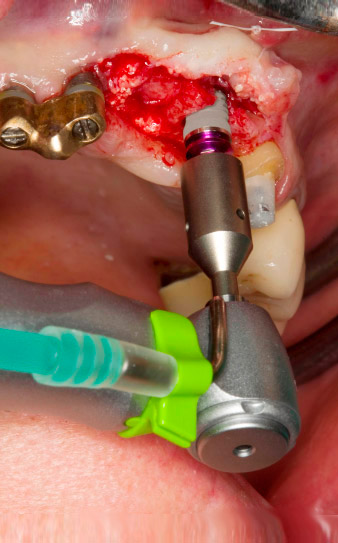

In the scope of the exposure for the implantation at position 23, the implant stability was measured with the W&H Osstell ISQ (implant stability quotient) module integrated in the device four months later.

This was done by screwing in the corresponding measuring post (SmartPeg) for the implant system and positioning the probe at a distance of 3-5 mm from the front side of the measuring post (Fig. 7).

In this case study, we also employed the optionally integrable W&H Osstell ISQ module (Fig. 7). As the implant was covered when healed, it was possible to confirm when the process had successfully completed (implant 22). If immediate or early loading is planned, the module – in combination with the registered torque – can be used to check the requisite primary stability. All the data can be saved to the USB stick for each session and each implant. As such, not only the clinical but also the forensic requirements are fulfilled in an exemplary manner.